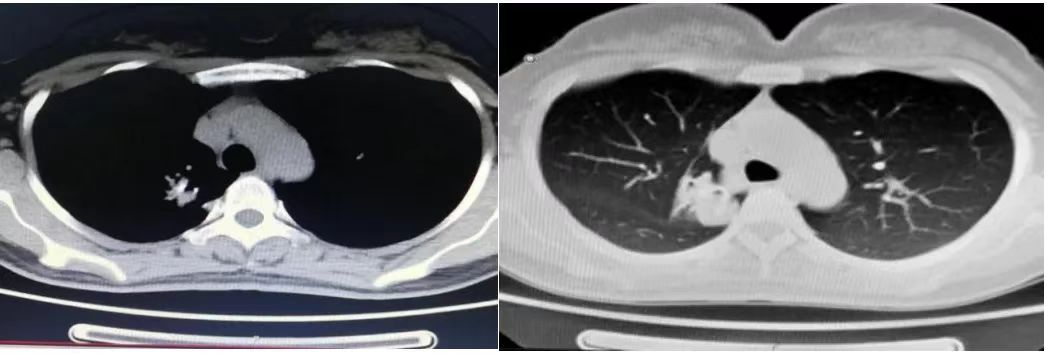

胸部CT:

右肺上叶肺门旁见软组织团块影(8.0cm×5.0cm)

右肺门及纵隔淋巴结肿大

双肺多发小结节,考虑转移瘤可能

图1 2015年7月胸部CT